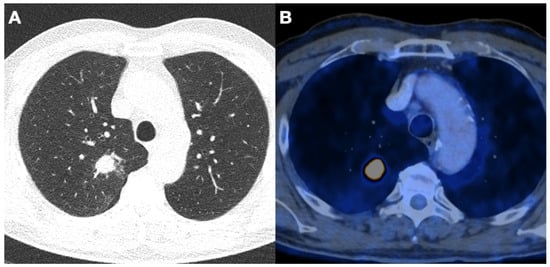

3.5. Incidental Findings

| Carcinomas (Number, (%)) | 4 (4) | |

| Adenocarcinoma | 3 (3) | |

| Squamous cell carcinoma | 1 (1) | |